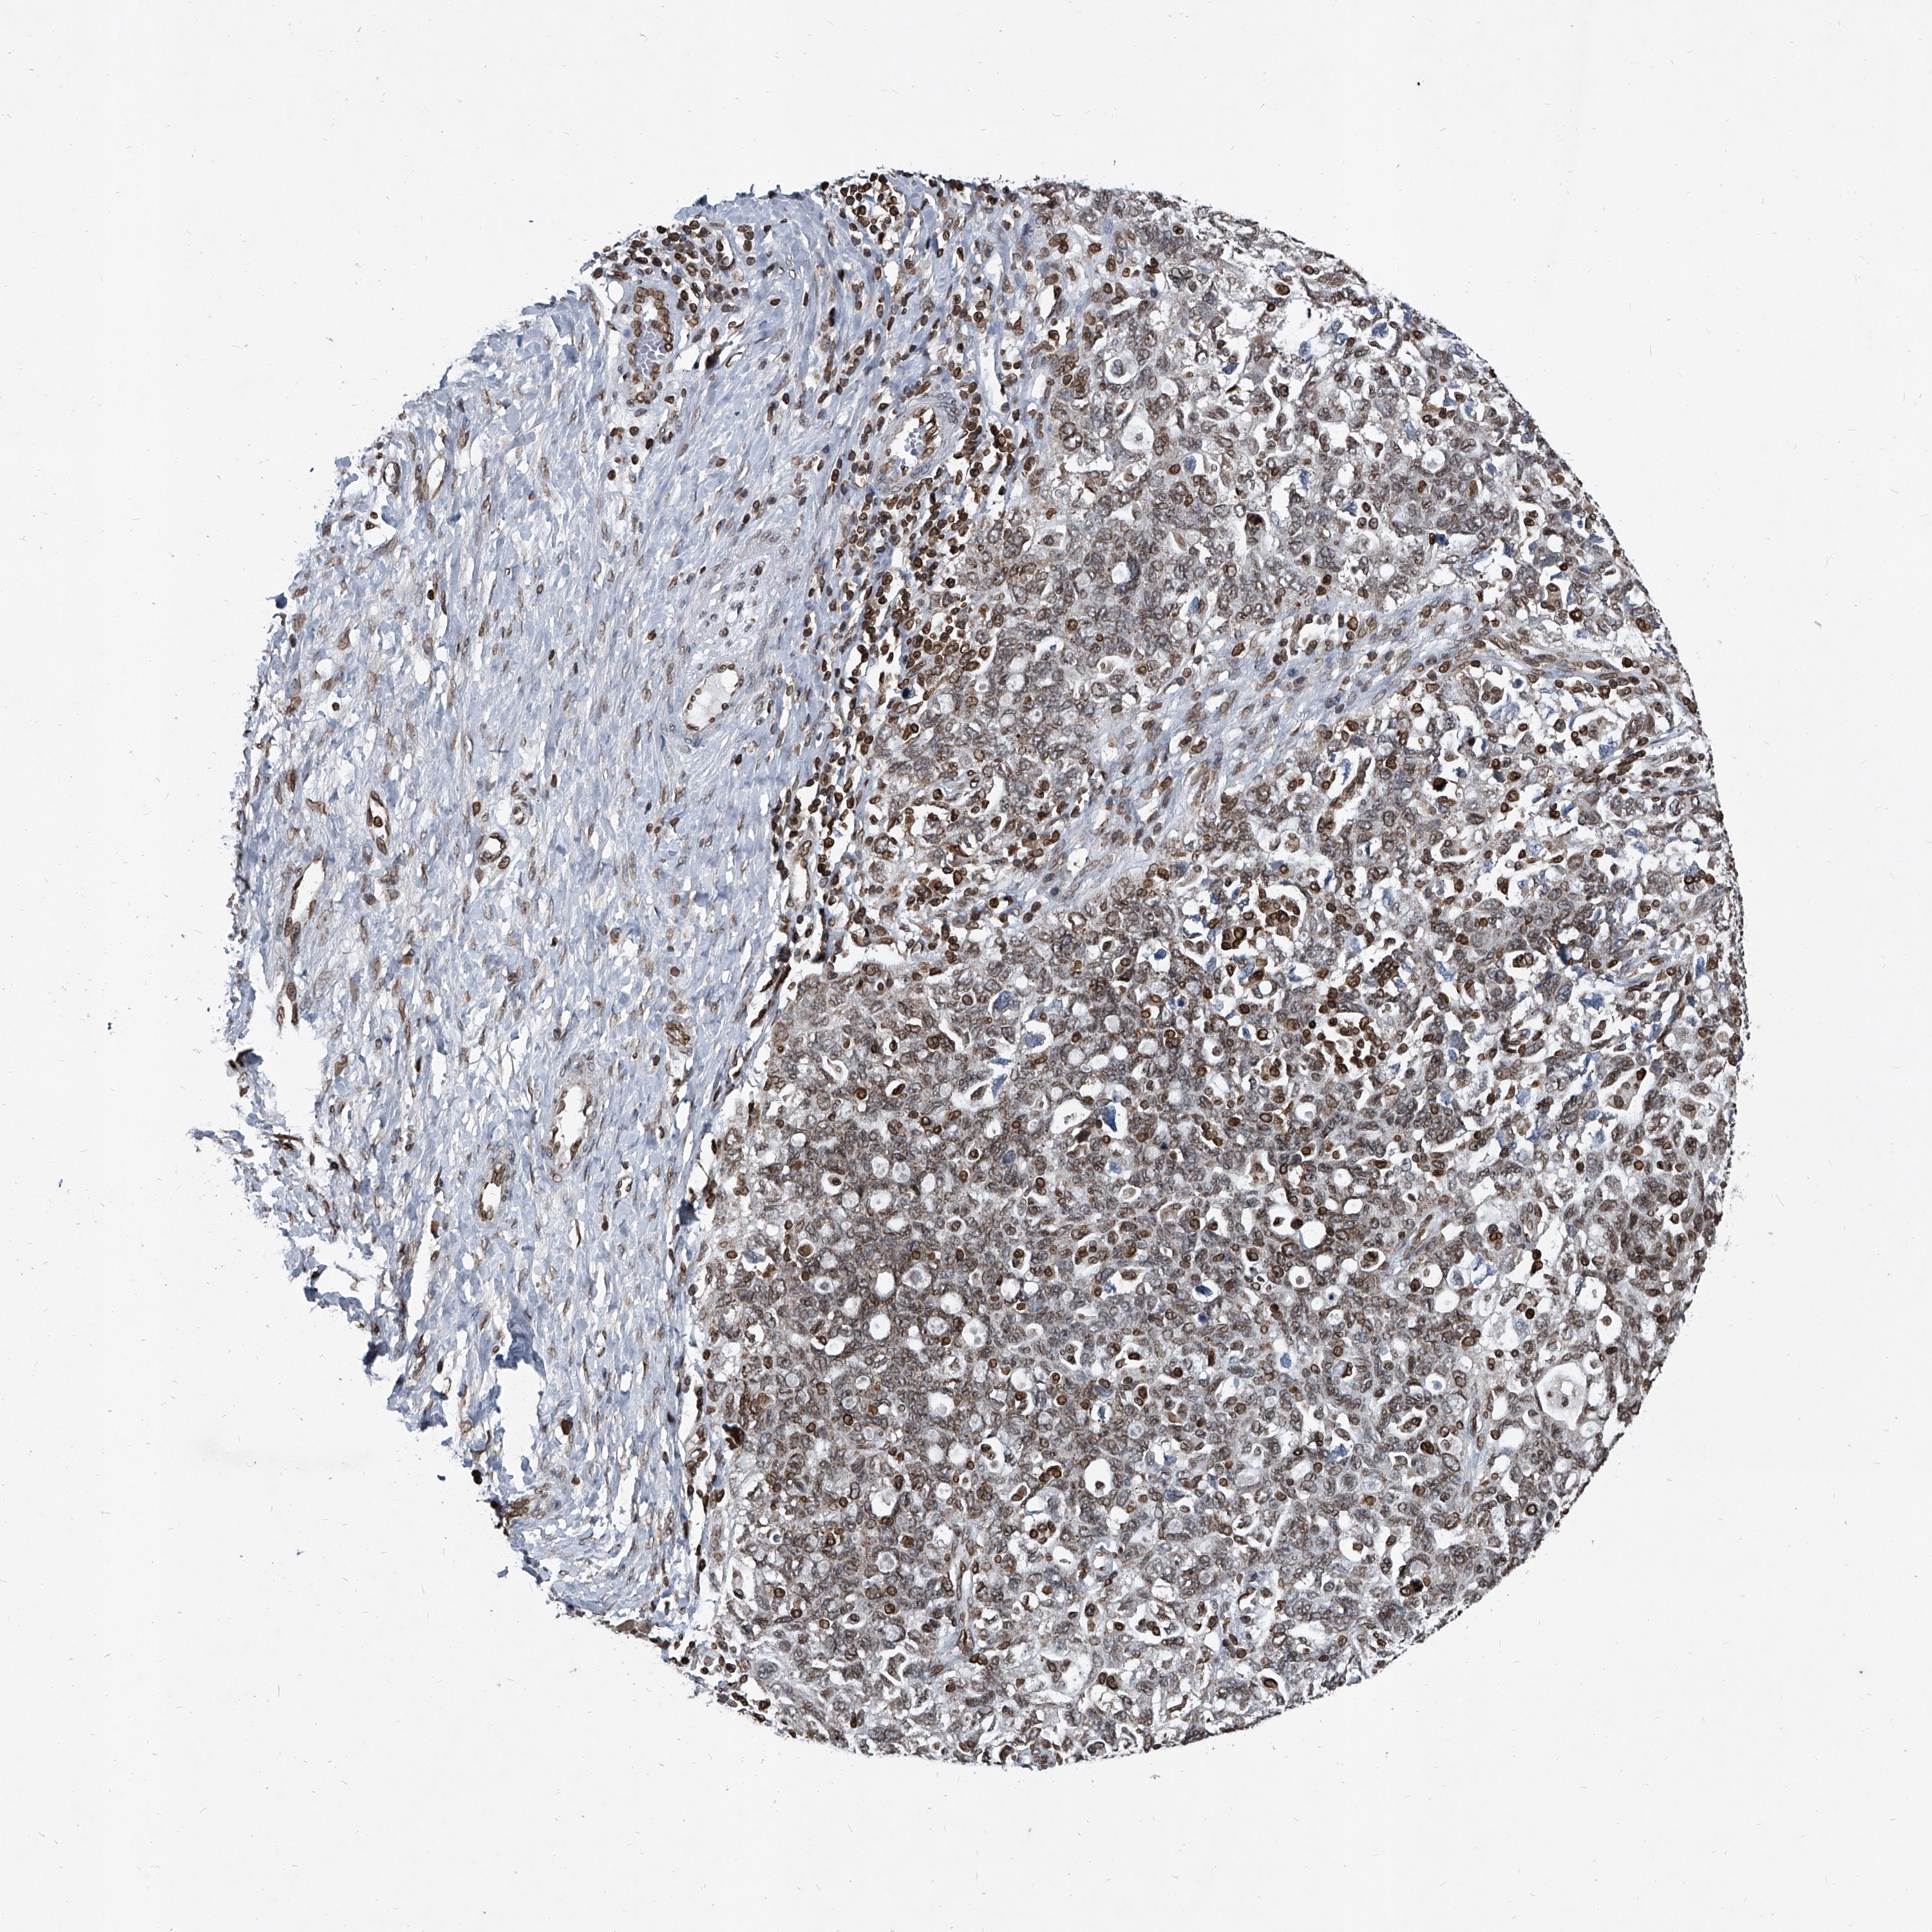

PHF20